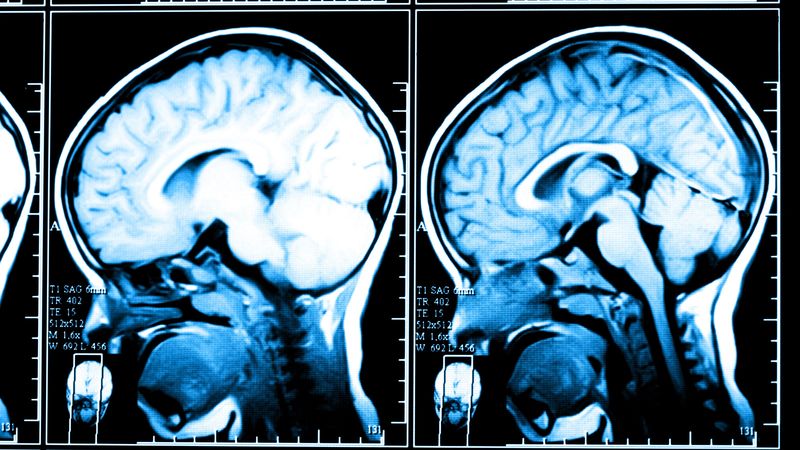

薬剤師などの仕事をしてきた女性は23歳の時に7歳上の一級建築士の夫と結婚。子供はいなかったが、とてもいい関係を続けてきた。ところが、夫が67歳の時、突如としてめまい・ふらつき・転倒が多発。医師は脳の画像などを見た後、「治りません。難病です」と聞いたことのない病名を告げた――。(前編/全2回)